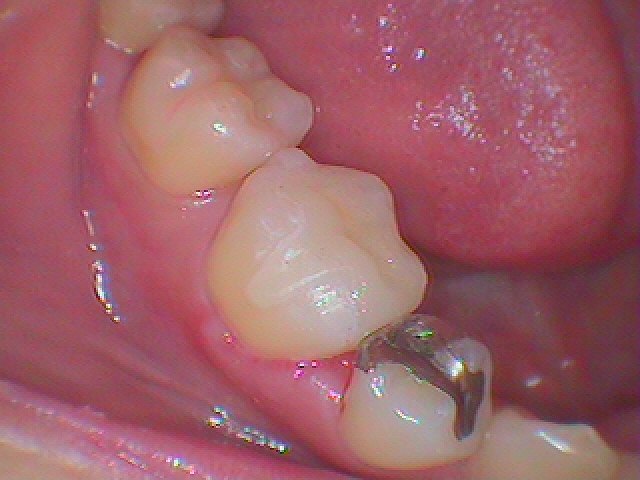

右上の5番部の遠心部に虫歯が存在していました

虫歯を除去してCR樹脂にて覆罩を行っています